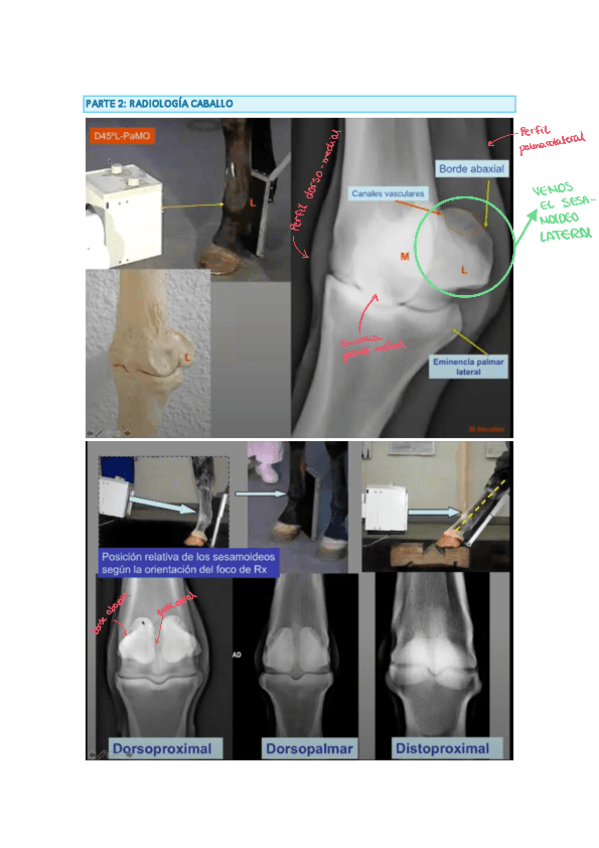

He publicado nuevos apuntes de 3º Diagnóstico Por la Imagen: Proyecciones-Radiograficas-de-menudillocanacarpo-caballo.pdf